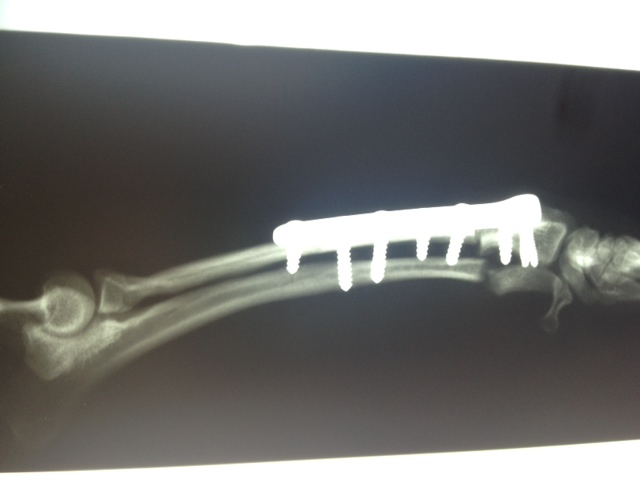

Felipas erste Operation

06Heute hatte Felipa ihren ersten OP-Termin.

Wir waren alle sehr aufgeregt. Und selbst der erfahrene Arzt meinte, es sei eine ungewöhnliche Aktion, denn normalerweise weist nur ein Pfötchen so starke Anomalien auf. Er hatte es noch nicht, dass beide operiert werden müssen.

Felipa war relativ unbeeindruckt von der ganzen Geschichte und tanzte schon kurz nach dem Eingriff wieder auf dem Tisch herum.

In sechs Wochen erfolgt dann die zweite OP.